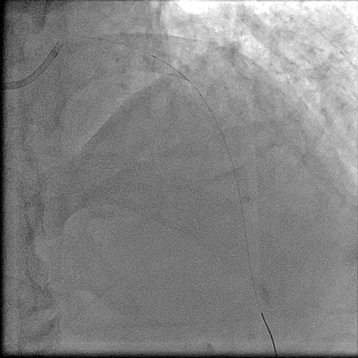

【临床病例】心肌梗死、心力衰竭患者心室率控制不佳怎么办?--新型If通道阻滞剂的应用

文章来自:中山二院心脏病MDT 叶伟斌 张坤